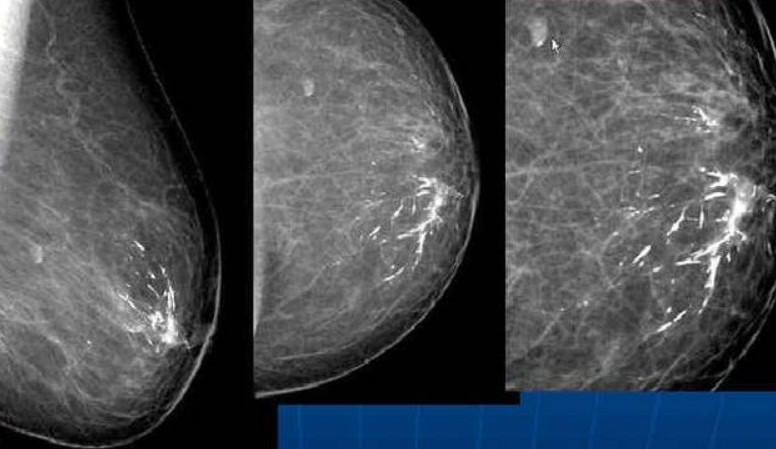

基本上,钙化大多没有任何症状,和肿瘤也无太大关联。部分脏器,如乳腺、肾脏和胰腺的肿瘤常发生钙化,且钙化形态和分布对评价恶性肿瘤存在的可能性有较大意义,以上部位尤其是乳腺的钙化灶通常需要做进一步评价。